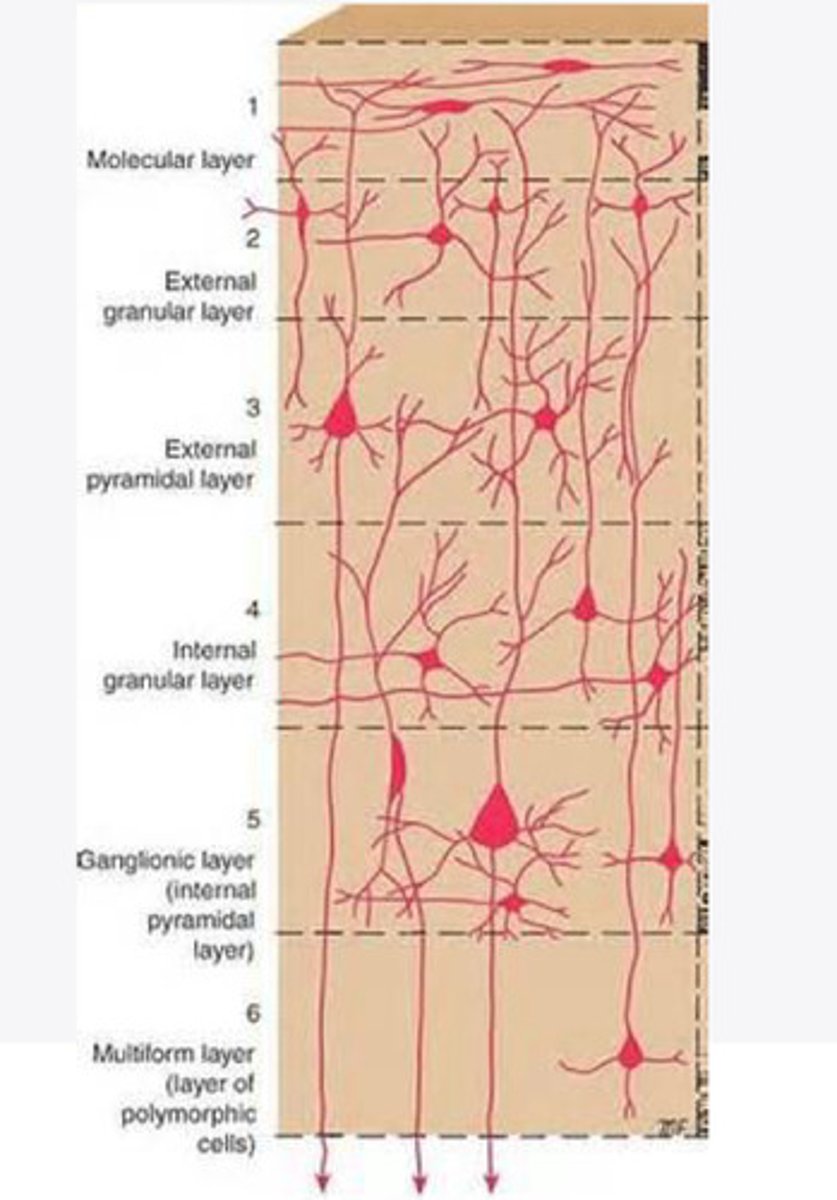

divided into 6 distinct layers, due to varying densities of cell body types within each layer

The cortex of the brain is divided into how many layers? Why is it divided into layers?

Layers of the cortex of the brain pic

2 and 4

What are the layers of the cortex that are associated with input?

3 and 5

What are the layers of the cortex that are associated with output?

molecular layer

What is the name of Layer 1 of the cortex of the brain?

very few cells

Does Layer 1 of the cortex have a lot or few cells?

receives dendrites from internal layers so it may actually function as a coordinating center where layers can communicate action

What does Layer 1 of the cortex do?

1

Every layer sends densities to Layer ____?

1

What layer serves as the "water cooler" of the brain?

external granular layer

What is the name for layer 2 of the cortex of the brain?

receives input from other cortical regions

What is the function of Layer 2 of the Cortex of the brain?

Stellate

What type of cells (stellate/pyramidal) would be most concentrated in Layer 2?

external pyramidal layer

What is the name for layer 3 of the cortex of the brain?

sends output to the other cortical layers

What is the function of Layer 3 of the cortex of the brain?

pyramidal

What type of cells (stellate/pyramidal) would be most concentrated in Layer 3 of the brain?

Layers 2 and 3

What layers are associated with association and commissural fibers?

Layer 3 - axons of cell bodies

Layer 2 - synapse into target areas in Layer 2

What part of the axons is in Layer 2/ in layer 3?

Layer 3 - external pyramidal layer

All axonal cel bodies for association and commissural fibers lie within what layer of the Cortex of the brain?

internal granular

** or called the striate cortex because it is so thick that you can see a line through this layer even in unstrained brain slides

What is the name for the 4th layer of the cortex of the brain?

receives input from the thalamus, geniculocortical layer, and other brainstem areas

What is the function for the 4th layer of the Cortex of the brain?

very thick within the vision, auditory, and somatosensory areas

Is Layer 4 thick or thin within SENSORY areas of the cortex?

Internal pyramidal

What is the name for Layer 5 of the cortex of the brain?

sends axons to the brainstem (corticobulbar) and spinal cord (corticospinal)

What is the function of Layer 5 of the cortex of the brain?

in motor areas of the cortex?

Where is layer 5 very thick in the brain?

the frontal lobe -- very motor heavy

What lobe of the brain will have a thick layer 5 of the cortex of the brain?

the multiform layer

What is the name of layer 6 of the cortex of the brain?

-sends axons back to the thalamus through corticogeniculate fibers

-modulates what information the thalamus sends to the cortex to control the strength of the signal received and modulate what you pay attention to

What is the function of layer 6 of the cortex of the brain?

no

Is layer 6 a motor layer?